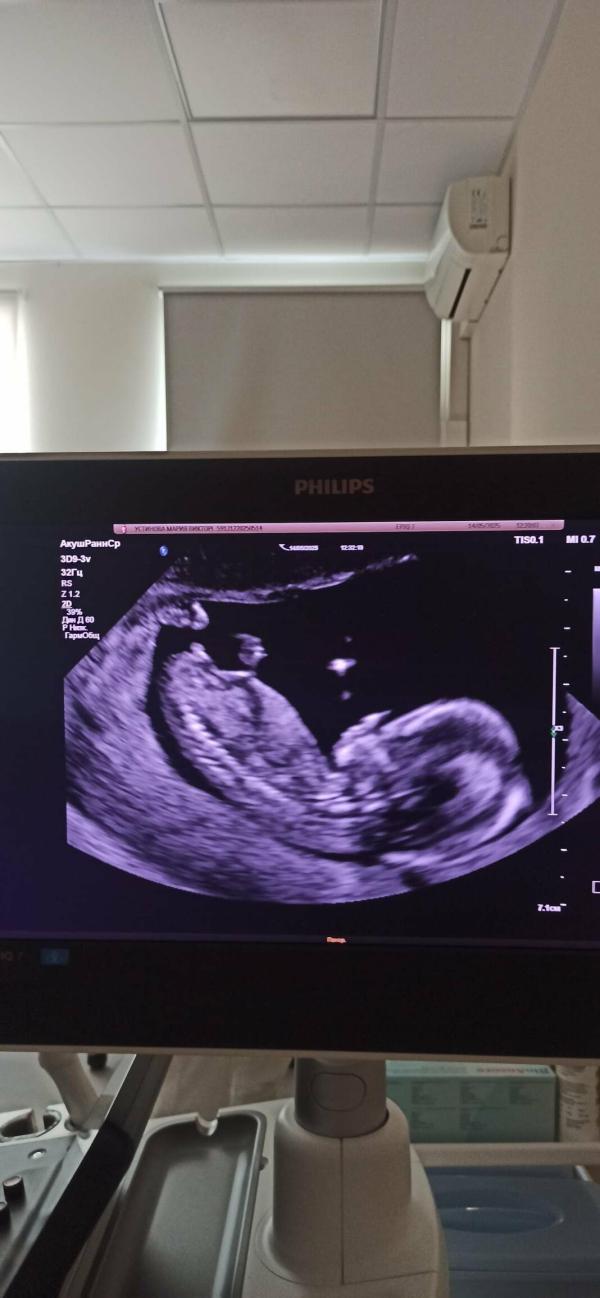

Maria ·Мама двоих (6 лет, 7 лет), ждёт третьего

Девы, кого видите?

Ставлю на девочку, угол между половым бугорком и позвоночником как у моей по снимкам)

У мальчика бугорок наверх торчит

Девочка по бугорку

Девочка,у мальчиков бугорок к верху торчит